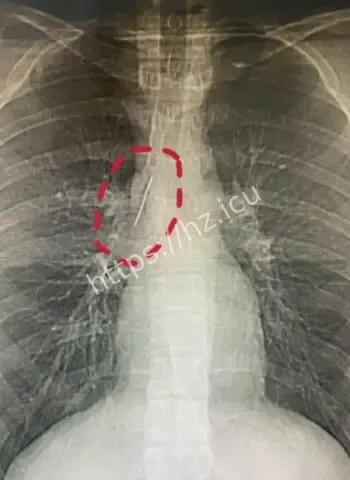

哎呦喂这事儿听起来就跟天方夜谭一样,一个安徽的17岁小伙子平时活蹦乱跳的,准备去参军体检,结果医生一照X光片子,眼睛直接瞪圆了,胸腔里居然稳稳当当藏着一根5厘米长的缝衣针。这针估计从小时候就钻进去了,整整17年啊,小伙子吃饭睡觉打球跑步啥都没耽误,身体愣是没闹过一点别扭。换成别人早疼得满地打滚了,他倒好,像没事人似的,这运气简直逆天到让人羡慕嫉妒恨。 想想这17年里,针就这么安静待着,没移位没发炎没刺着要害,估计是身体自动给它裹了一层保护膜,把它当成了自家摆设。

最离谱的是,这针很可能他1岁那会儿不小心扎进去的。小宝宝那时候到处乱爬乱抓,说不定妈妈正缝衣服,他一扑腾就中招了,结果针就这么悄无声息地进了胸腔。17年过去,他从奶娃娃长成大小伙,针却一直老老实实待着,没引起任何不舒服。平时感冒发烧都没多想过胸口,这适应力也太强了吧。 从道理上讲,小孩子身体正长着,组织慢慢把针包得严严实实,像给它建了个小房子隔离起来。没碰着肺叶心脏血管,纯靠运气加体质,简直是活生生的人体奇迹。

参军体检意外发现胸腔惊人异物

参军体检本来是查身体合不合格,谁知道成了挖宝现场。X光一扫,医生估计当时就傻眼了,这么大一根针亮闪闪地躺在胸腔里,小伙子自己都蒙圈了,心想我这身体里藏了啥秘密武器啊。幸好发现及时,要不然以后训练强度一大,万一针跑偏了,后果真不敢想。 这事儿也给大伙提了个醒,重要关口体检千万别马虎,尤其是参军这种人生大事,啥隐藏问题都能揪出来。小伙子估计现在又惊又喜,喜的是没出大事,惊的是自己居然带了17年“隐形伴侣”。

深入扒一扒,这针为啥能跟身体和平共处这么久呢。首先位置挑得好,没扎着要害器官,胸腔空间大给它留了余地。其次人体有自我保护本能,会分泌纤维组织慢慢把它包裹住,防止感染和移位。小时候扎入,身体还在发育,适应起来更容易。再次可能没带细菌进去,运气成分占大头。 这案例搁医学上都算罕见,值得研究研究,说不定以后处理类似异物就有新办法了。不过小伙子以后肯定得做个小手术取出来,不然总是个小隐患。希望手术顺顺利利,他的参军梦还能接着追,这段经历以后说出去绝对是别人听不够的传奇。